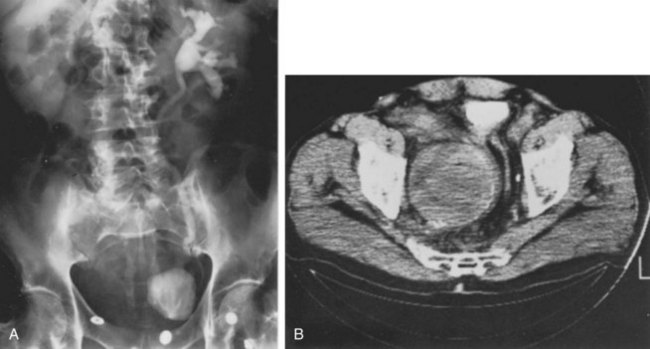

Currently, CT scanning is most frequently used to evaluate patients with an AAA that may demonstrate associated hydronephrosis (Fig. 40–16A and B). Ureteral findings associated with AAA vary. The ureters may be pushed laterally on both sides, or one side may deviate laterally while the opposite side is drawn medially within the perianeurysmal inflammation, or both may be medially deviated. Some have noted that lateral deviation of the ureter with AAA is usually not associated with obstruction (Labardini and Ratliff, 1967). The medial deviation of the ureter associated with the desmoplastic reaction of inflammatory aneurysms (IAAA), however, carries a more significant risk of ureteral obstruction. Although IAAA represents only between 4% and 15% of AAAs, the associated retroperitoneal desmoplastic reaction significantly increases the risk of ureteral obstruction, which has been reported in 21% of this cohort (Pennell et al, 1985; Arroyo et al, 2003).

Figure 40–16 A and B, Computed tomography scans demonstrate extensive retroperitoneal fibrosis associated with aneurysm of the abdominal aorta.

Iliac artery aneurysms can cause ureteral obstruction, which may even lead to renal failure (Ochoa Urdangarain et al, 2006). Ureteral obstruction has been reported in 35% of those with common iliac artery aneurysms and 19% of those involving the internal iliac artery. An iliac artery aneurysm should be suspected if a pulsatile mass is palpated on rectal examination (Marino et al, 1987). The diagnosis can be made with various imaging studies including ultrasonography, MRI, and CT (Fig. 40–17A and B). Ureteral obstruction may be due to extrinsic compression or localized inflammation (Mineta et al, 2004).

Figure 40–17 Right ureteral obstruction secondary to an aneurysm of the right hypogastric artery. A, Intravenous urogram demonstrates delayed visualization of the right kidney and marked deviation of the urinary bladder. B, Computed tomography scan demonstrates a large aneurysm. Note calcification of the wall.